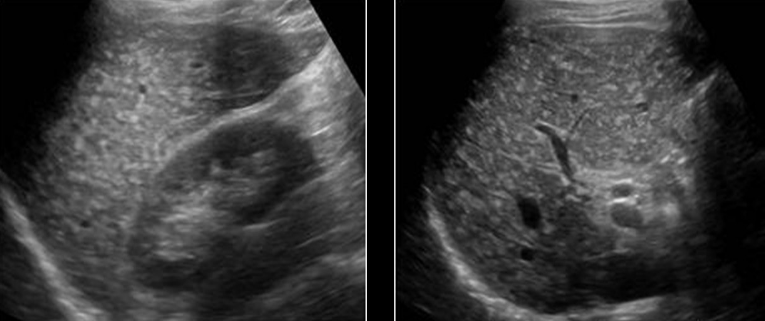

Identify this image.

Hemangioma seen with “mass effect” on other structures and vessels

Fatty infiltration seen with no displacement of other tissues